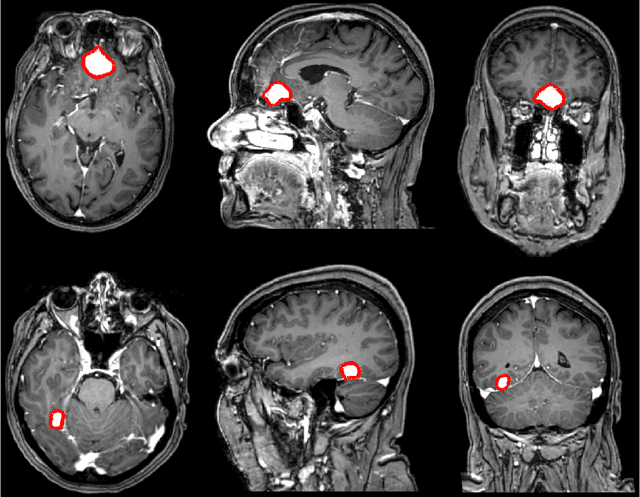

Abstract:Meningiomas are the most common type of primary brain tumor, accounting for approximately 30% of all brain tumors. A substantial number of these tumors are never surgically removed but rather monitored over time. Automatic and precise meningioma segmentation is therefore beneficial to enable reliable growth estimation and patient-specific treatment planning. In this study, we propose the inclusion of attention mechanisms over a U-Net architecture: (i) Attention-gated U-Net (AGUNet) and (ii) Dual Attention U-Net (DAUNet), using a 3D MRI volume as input. Attention has the potential to leverage the global context and identify features' relationships across the entire volume. To limit spatial resolution degradation and loss of detail inherent to encoder-decoder architectures, we studied the impact of multi-scale input and deep supervision components. The proposed architectures are trainable end-to-end and each concept can be seamlessly disabled for ablation studies. The validation studies were performed using a 5-fold cross validation over 600 T1-weighted MRI volumes from St. Olavs University Hospital, Trondheim, Norway. For the best performing architecture, an average Dice score of 81.6% was reached for an F1-score of 95.6%. With an almost perfect precision of 98%, meningiomas smaller than 3ml were occasionally missed hence reaching an overall recall of 93%. Leveraging global context from a 3D MRI volume provided the best performances, even if the native volume resolution could not be processed directly. Overall, near-perfect detection was achieved for meningiomas larger than 3ml which is relevant for clinical use. In the future, the use of multi-scale designs and refinement networks should be further investigated to improve the performance. A larger number of cases with meningiomas below 3ml might also be needed to improve the performance for the smallest tumors.

Abstract:Automatic and consistent meningioma segmentation in T1-weighted MRI volumes and corresponding volumetric assessment is of use for diagnosis, treatment planning, and tumor growth evaluation. In this paper, we optimized the segmentation and processing speed performances using a large number of both surgically treated meningiomas and untreated meningiomas followed at the outpatient clinic. We studied two different 3D neural network architectures: (i) a simple encoder-decoder similar to a 3D U-Net, and (ii) a lightweight multi-scale architecture (PLS-Net). In addition, we studied the impact of different training schemes. For the validation studies, we used 698 T1-weighted MR volumes from St. Olav University Hospital, Trondheim, Norway. The models were evaluated in terms of detection accuracy, segmentation accuracy and training/inference speed. While both architectures reached a similar Dice score of 70% on average, the PLS-Net was more accurate with an F1-score of up to 88%. The highest accuracy was achieved for the largest meningiomas. Speed-wise, the PLS-Net architecture tended to converge in about 50 hours while 130 hours were necessary for U-Net. Inference with PLS-Net takes less than a second on GPU and about 15 seconds on CPU. Overall, with the use of mixed precision training, it was possible to train competitive segmentation models in a relatively short amount of time using the lightweight PLS-Net architecture. In the future, the focus should be brought toward the segmentation of small meningiomas (less than 2ml) to improve clinical relevance for automatic and early diagnosis as well as speed of growth estimates.